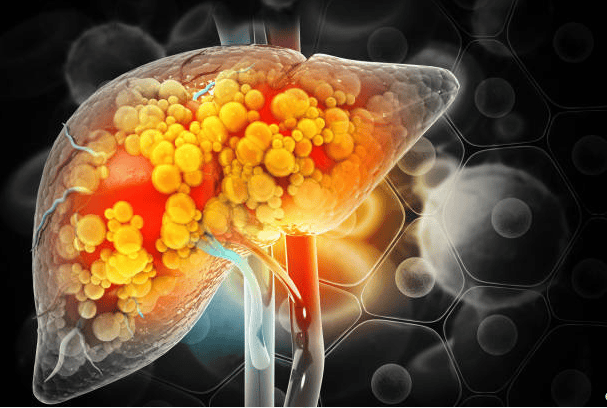

La depuració hepàtica és una forma controlada d’ajudar a l’organisme a què elimini toxines, la seva funció és accelerar la neteja hepàtica que es produeix al fetge de forma natural perquè el cos tingui el millor nivell d’eficiència, sobretot si per la nostra forma de vida acumulen un excés de toxines, o tenim els nostres òrgans inflamats i necessiten un suport per funcionar correctament.

Per si no n’hi hagués prou, el fetge té a veure amb més de cinc-centes funcions vitals en el nostre cos. Les més importants són: la producció biliar, la regulació del metabolisme dels lípids, produeix proteïnes a la sang i regula els aminoàcids, transforma el sucre en glucogen (fonamental pel rendiment esportiu), sintetitza el colesterol, emmagatzema el ferro, combat els bacteris que circulen per la nostra sang, regula la temuda coagulació sanguínia, i, en definitiva, depura el nostre cos, eliminant substàncies perilloses com ho són l’alcohol o les substàncies tòxiques del medicament. Mireu la importància d’aquest òrgan vital que emmagatzema el 13% de la nostra sang.